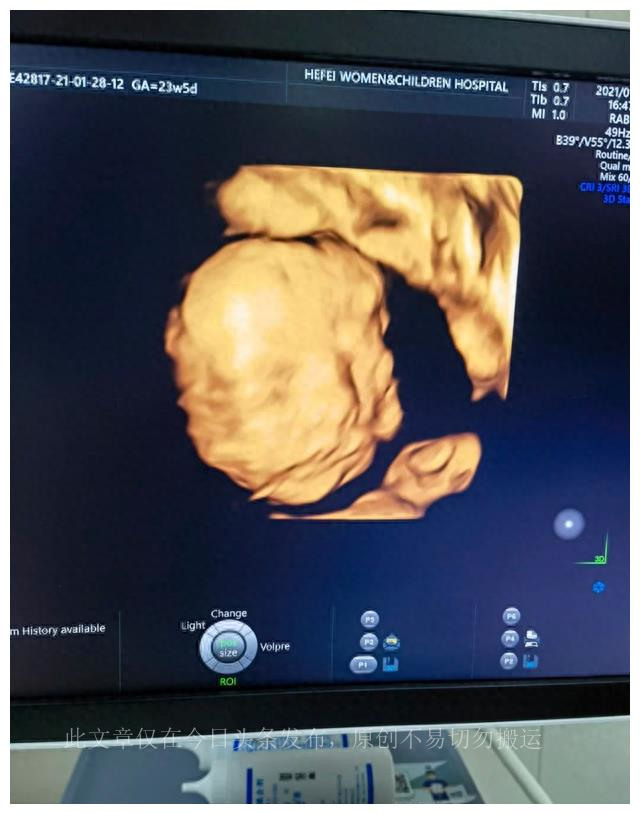

第一次四维检查是在怀孕23周零3天进行的,这是在公立医院完成的。尽管约定在下午,但宝宝却表现得非常不配合,使整个过程变得有些曲折。

第一次检查时,宝宝没有正确地转动,导致医生难以获得清晰的图像。医生尽力采集数据后,建议产妇去走动,这有助于激发胎儿的活动。第二次检查半小时后进行,但宝宝仍然没有转过来。产妇尝试了一些巧克力,然后进行了第三次检查。这一次,宝宝终于转过来了,医生成功地获得了所需的数据,这对排除胎儿畸形非常重要。最终,这次四维检查以胎儿的健康状态而告终。